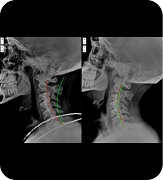

Data guided health evaluation that examines underlying contributors to symptoms and shapes individualized care plans.